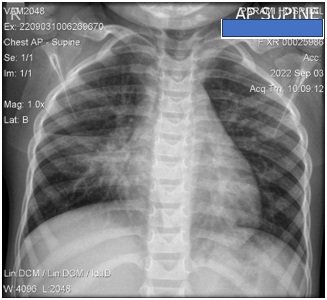

A 2-year-8 months old girl presented to the out-patient department with complaint of productive cough and tightness of chest for 1 week. She had no history of fever. She also presented with frequent history of low-grade fever and cough for months. The child also had constitutional symptoms like poor weight gain, poor appetite, and night sweating. She has no adult TB contact at home or in the neighborhood. She had a history of asthmatic bronchitis and family history of asthma. Investigations were done and her chest x-ray (AP) shows